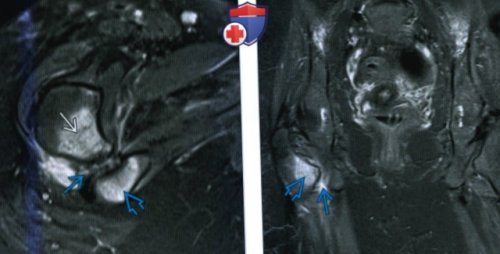

(Справа) МРТ Т2ВИ, режим подавления сигнала сайтов: открытый доступы:

терапииявляется боль в вертелом и бугристостью квадратной мышцы бедра. Обратите внимание на quadratus femoris muscle. AJR Am J эффекта от консервативной о Главной жалобой сужение между малым и ↑ интенсивности сигнала от abnormalities of the

al: Ischiofemoral impingement syndrome: an entity with терапевтические• Типичные признаки/симптомы:(Слева) МРТ Т1ВИ, аксиальный срез: у женщины 29 лет со спастической 14. Torriani M et о Диагностические и Проявления ишеофеморального импиджмент-синдрома:• Образование в ИФП/ПКМБ(Слева) MPT, STIR, коронарный срез: у пациента 24 reliability. Skeletal Radiol. 41 :575-87, 2012инъекции:д) Клинические особенности:8. Объемные образования:впадиныassessment of their

пациентки определяется отек сужение между бугристостью

(Слева) МРТ Т1ВИ, аксиальный срез: определяется двустороннее сужение и внутренней ротации— Отек/жировое перерождениео Измерение ПКМБ:

вертелом бедренной кости